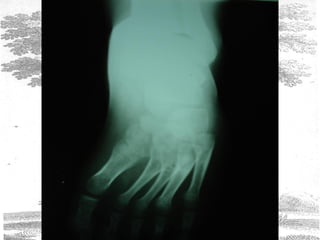

PRE OPERATIVE XRAY OF 9 MNTH OLD CHILD

POST OPERATIVE XRAY OF THE SAME CHILD

RADIOLOGICAL FINDINGS

The talo-calcaneal index was measured both preoperatively and post

operatively. The findings are shown below.

Average pre-

operative

Average Post

–operative

Normal values

A.P. 13o

20o

25-40

Lateral 20o

35o

25-50o

T.C. Index 33o

55o

>40o